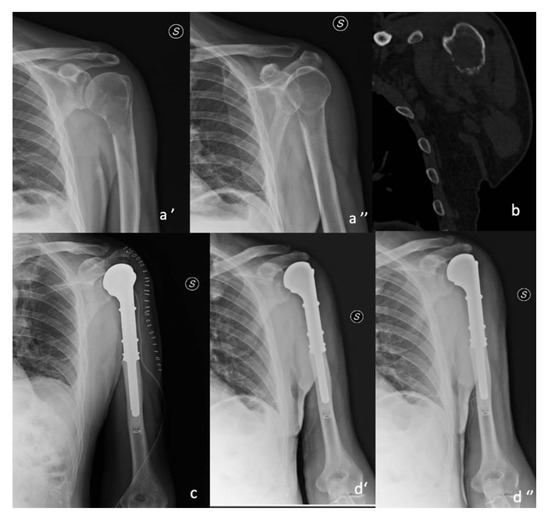

Functional Outcomes and Shoulder Instability in Reconstruction of Proximal Humerus Metastases

3.2. Resection Surgery

3.3. Surgery Approach